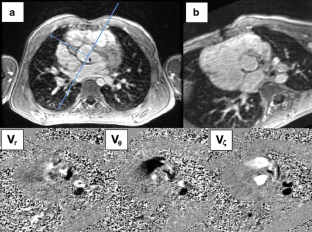

Fig. 1